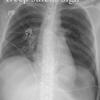

Deep sulcus sign.

Supine pneumothorax